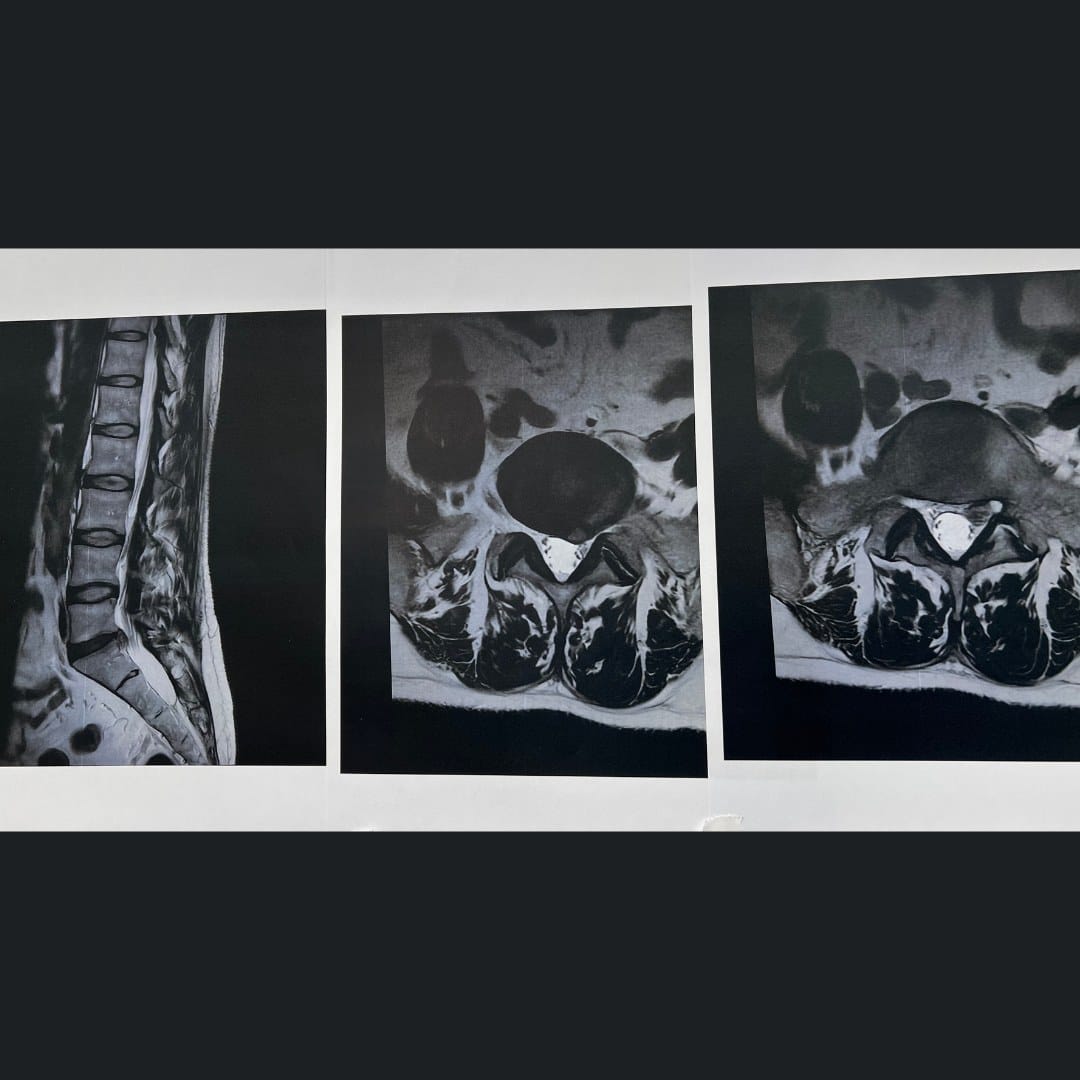

Περιστατικό

Αντιμετωπίστηκε με Μικροδισκέκτομη Ο5-Ι1 Αρ .